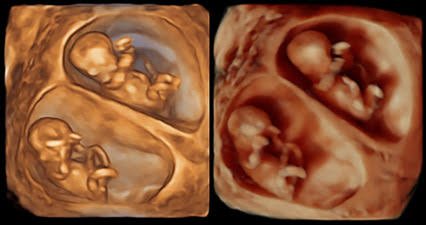

Perbedaan USG 2D, USG 3D, dan USG 4D: Memahami Teknologi Pemindaian Janin

USG Apa yang Lebih Unggul? Ini Penjelasannya